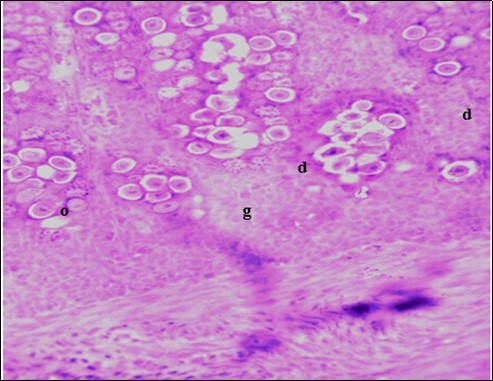

In this study, the reduction in oocyst count observed in the treated group was compared with amprolium could be attributed to the presence of a bioactive compounds azadiractin A which is known to bind membrane cholesterol, altering the integrity of the parasite membrane, resulting in loss of homeostasis and eventual death of the parasite 29]. Also, limonoids contained in NeemAzal® inhibit protein digestion and uptake of vitamins and minerals by the parasites in the gut 17. This action results in impaired nutrient utilization, reduced growth, and multiplication of the parasite which could contribute to the reduced oocyst count observed. Extracts of neem and mahogany when used individually have been reported to reduce oocyst count in avian coccidiosis 11,12. The observed reduction in oocyst count and the significant increase in weight gain of the birds when treated with NeemAzal®, as compared with the negative control group could probably be due to the inhibition of inflammation in the intestinal mucosa which is suggestive of an increased nutrient absorption across the intestinal wall and enhanced feed conversion ratio compared to the negative control this is in agreement with reports by Nwosu et al.12 and Biu et al.11 who also reported an increased weight gain and feed conversion ratio in birds treated with only Khaya senegalensis extracts and Azardiractaindica, respectively. The observed increase in RBC and haemoglobin concentration is indicative of the erythropoieticability of the NeemAzal®, which is beneficial since the Eimeria parasite in the epithelia of the intestines causes bloody diarrhoea and consequently anaemia (Table 1). This finding is in consonance with 15 who reported an anti-anaemic effect of Khaya Senegalensis on phenyl hydrazine-induced anaemia in rats. Neem has been shown to possess anti-anaemic properties in rats 14. The significant increase in mean weight gain in treated birds when compared to the negative control is possibly due to the inhibition of inflammation in the intestinal mucosa which is suggestive of an increased nutrient absorption across the intestinal wall and enhanced feed conversion ratio compared to the negative control. Nwosu et al.12 and Biu et al.11 reported an increased weight gain and feed conversion ratio in birds treated with only Khaya Senegalensis andAzadiractaindica extracts, respectively. In a similar study, Neem acts like toltrazuril exhibiting anticoccidial. In addition, exposure of broiler chickens to 20000 Oocysts of Eimeria tenellacaused generalized degeneration of the caecal glands with massive Oocysts and gametocyts within the caecal glands with fibrosis (Figure 3, Figure 4 & Figure 5), however, broiler chickens treated with NeemAzal® post exposure to 20000 Oocysts of Eimeria tenella, shows equal numbers of caecal tissues with non-observable histopathological lesions (Figure 4), possibly due to the antioxidant and anti-coccidian effects of NeemAzal®. The exact mechanism of action of neem against coccidian parasites is unknown, but a report by the National Research Council 1992 30, suggested that aqueous neem leaf extract, when taken orally, produces an increase in red cells, white blood cells and lymphocyte counts thus enhancing the cellular immune response, increasing antibody production and so most pathogens can be removed before they cause the symptoms associated with disease this was in agreement with this study as seen in Table a remarkable increase of the RBCs.

Figure 4.Photomicrograph of caecum of chick administered 20000 Oocysts of Eimeria tenella and untreated showing generalized degeneration of the caecal glands (d) with massive Ocysts (o) and gametocytes (g) largely within the caecal glands X250 (H&E).